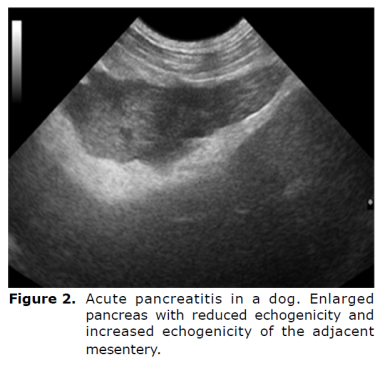

Pancreatitis is the most frequent disorder that affects the exocrine pancreas in dogs and requires safe and accurate techniques to obtain a quick prognosis and avoid complications to the patient. The complications most commonly observed are pancreatic cell death and regional blood supply loss, which can trigger systemic inflammatory response and lead to death (8). The ultrasonographic findings of pancreatitis vary with the severity, extent, and duration of inflammation in the tissue itself and in adjacent tissues. In acute pancreatitis, the organ is often enlarged, with reduced echogenicity, poor definition, and increased echogenicity of the adjacent mesentery (Figure 2). In some cases, free abdominal fluid may be present and the duodenum may be thickened and irregular. In dogs, the right pancreatic lobe is usually the most affected (13).